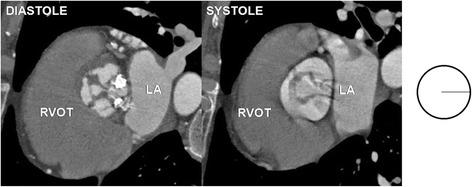

Bicuspid aortic valve (BAV) is the most common congenital cardiac anomaly. Other aortic valve variants are rare but are associated with an increased incidence of various pathologies of the aortic valve (AV). The aim of this study was to assess the AV function in regard to its anatomical variants morphology in patients who underwent 64-slice coronary computed tomography angiography (CCTA) for suspected or known coronary artery disease.

The results of 64-detector retrospective ECG-gated CCTA of 2053 patients (mean age 58 years; 1265 males) were analyzed retrospectively by experienced cardiovascular radiologist. Coronary anatomy (with coronary artery dominance) and the extent of occlusion in the coronary arteries were assessed. Furthermore morphological and functional status of AV variants were analyzed. Among measured parameters were area at the level of AV annulus, orifice and tubular portion of the ascending aorta.

The AV was visualized in all CCTA studies and the analysis of its morphology and function was done in all patients. BAV was found in 19 patients (0.9 %), from which type 0 was diagnosed in five patients (0.2 %) and type 1 in 14 patients (0.7 %) - there was no patient with BAV type 2. Unicuspid (UAV) and quadricuspid (QAV) variant were both observed each in one patient (0.05 %). In rest of the patients from the study group tricuspid AV variant was recognized. Function of AV variants was mostly affected in BAV0 and UAV. Among patients with BAV1 there were patients with normal and abnormal function of AV. QAV variant did not deteriorate AV function. There was no difference in coronary artery disease and dominancy between different anatomical variants of AV.

During CCTA different valve variants can be detected and detailed analysis of valvular function can be proceeded. Larger values of annulus area, wider diameters of ascending aorta and more stenotic profile were observed in BAV 0, BAV 1 and UAV. Among AV variants morphology and function was mostly affected in patients with BAV 0 and UAV variants, while subjects with BAV1 had normal or abnormal function of the AV. Moreover, we noticed that QAV variant did not deteriorate AV function.